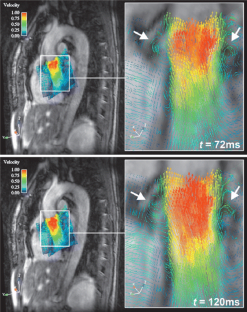

Fig. 3